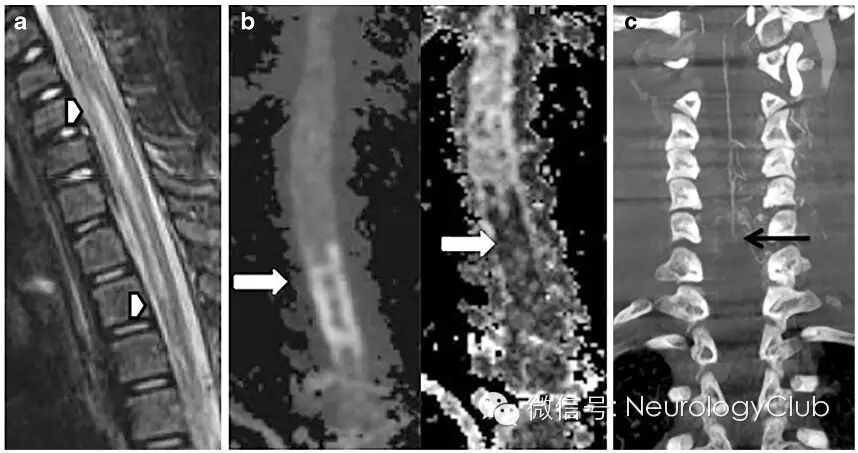

6脊髓梗死

(a:下颈段至上胸段异常信号;b:弥散张量成像及ADC提示病灶弥散受限;c:血管造影重建提示C6水平脊髓前动脉闭塞)

7脊髓血管畸形

(a:脊髓长节段高信号与异常流空现象;b:脊髓血管造影提示T5-8后椎管血管性病变;c:动态CT证实硬膜内和硬膜外静脉回流)